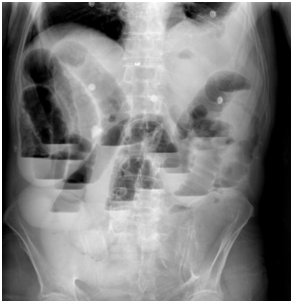

65-year-old man was admitted to our emergency department with nausea, vomiting, distension and colicky abdominal pain of 5days' duration. He had regulated hypertension and chronic obstructive pulmonary disease for fifteen years. He had undergone gastric and biliary surgery 25years ago. Physical examination revealed distension and tender abdomen with few poor bowel sounds especially in right mid-lower abdomen. Laboratory tests showed leukocytosis. Plain abdominal X-ray demonstrated the presence of a round hyperdense mass with calcified margins in the right lower quadrant as well as enlarged loops of small bowel (Figure 1) CT scan of the abdomen showed pneumobilia, a calcified mass impacted in the terminal ileum (Figure 2).

Figure 1 The plain radiography demonstrated multiple gas and fluid levels in intestines.

The clinical symptoms occasionally include nausea, vomiting, pain and hematemesis. Laboratory findings may demostrate impaired liver functions with high bilirubin and alkaline phosphophatase levels etc. The diagnosis is really a challenge for surgeon and usually depends on the radiographic findings. Preoperative conventional diagnostic tools generally do not demonstrate bilioenteric fistula and delay in diagnosis would be inevitable resulting higher morbidity and mortality rates. Whereas radiologic findings of mechanical bowel obstruction can easly be visualized in plane abdominal radiograms and computed tomography, pneumobilia would not be demonstrated in most cases.2,6,9 The classic Rigler’s triad of radiography includes mechanical bowel obstruction, pneumobilia, and an ectopic gallstone within bowel lumen.10 In our case, abdominal CT scan and plain radiograph also demonstrated dilated intestinal segments with stone opacity and gas in the biliary tree.